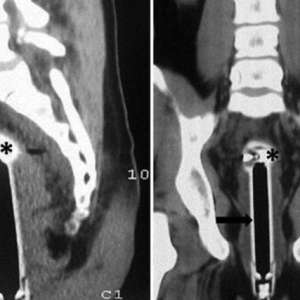

ШОКИРУЮЩИЙ СЛУЧАЙ: Юноша доставлен в больницу с инородным телом – морковью!

Вчерашним вечером в местную больницу поступил 16-летний подросток, из которого медики извлекли… морковь. По заявлению самого юноши, инцидент произошел, когда он, будучи без одежды, бегал по дому, потерял равновесие и упал таким образом, что овощ проник внутрь. Родители узнали о произошедшем только от персонала больницы, поскольку такие случаи подлежат обязательному уведомлению. Медики выражают надежду, что произошедшее действительно было случайностью.

Несмотря на всю нелепость ситуации, самое важное – состояние здоровья юноши. Хочется верить, что этот инцидент послужит ему уроком и заставит быть более внимательным к своим действиям и, возможно, пересмотреть некоторые привычки. Родителям же, безусловно, будет что обсудить за семейным столом в будущем.